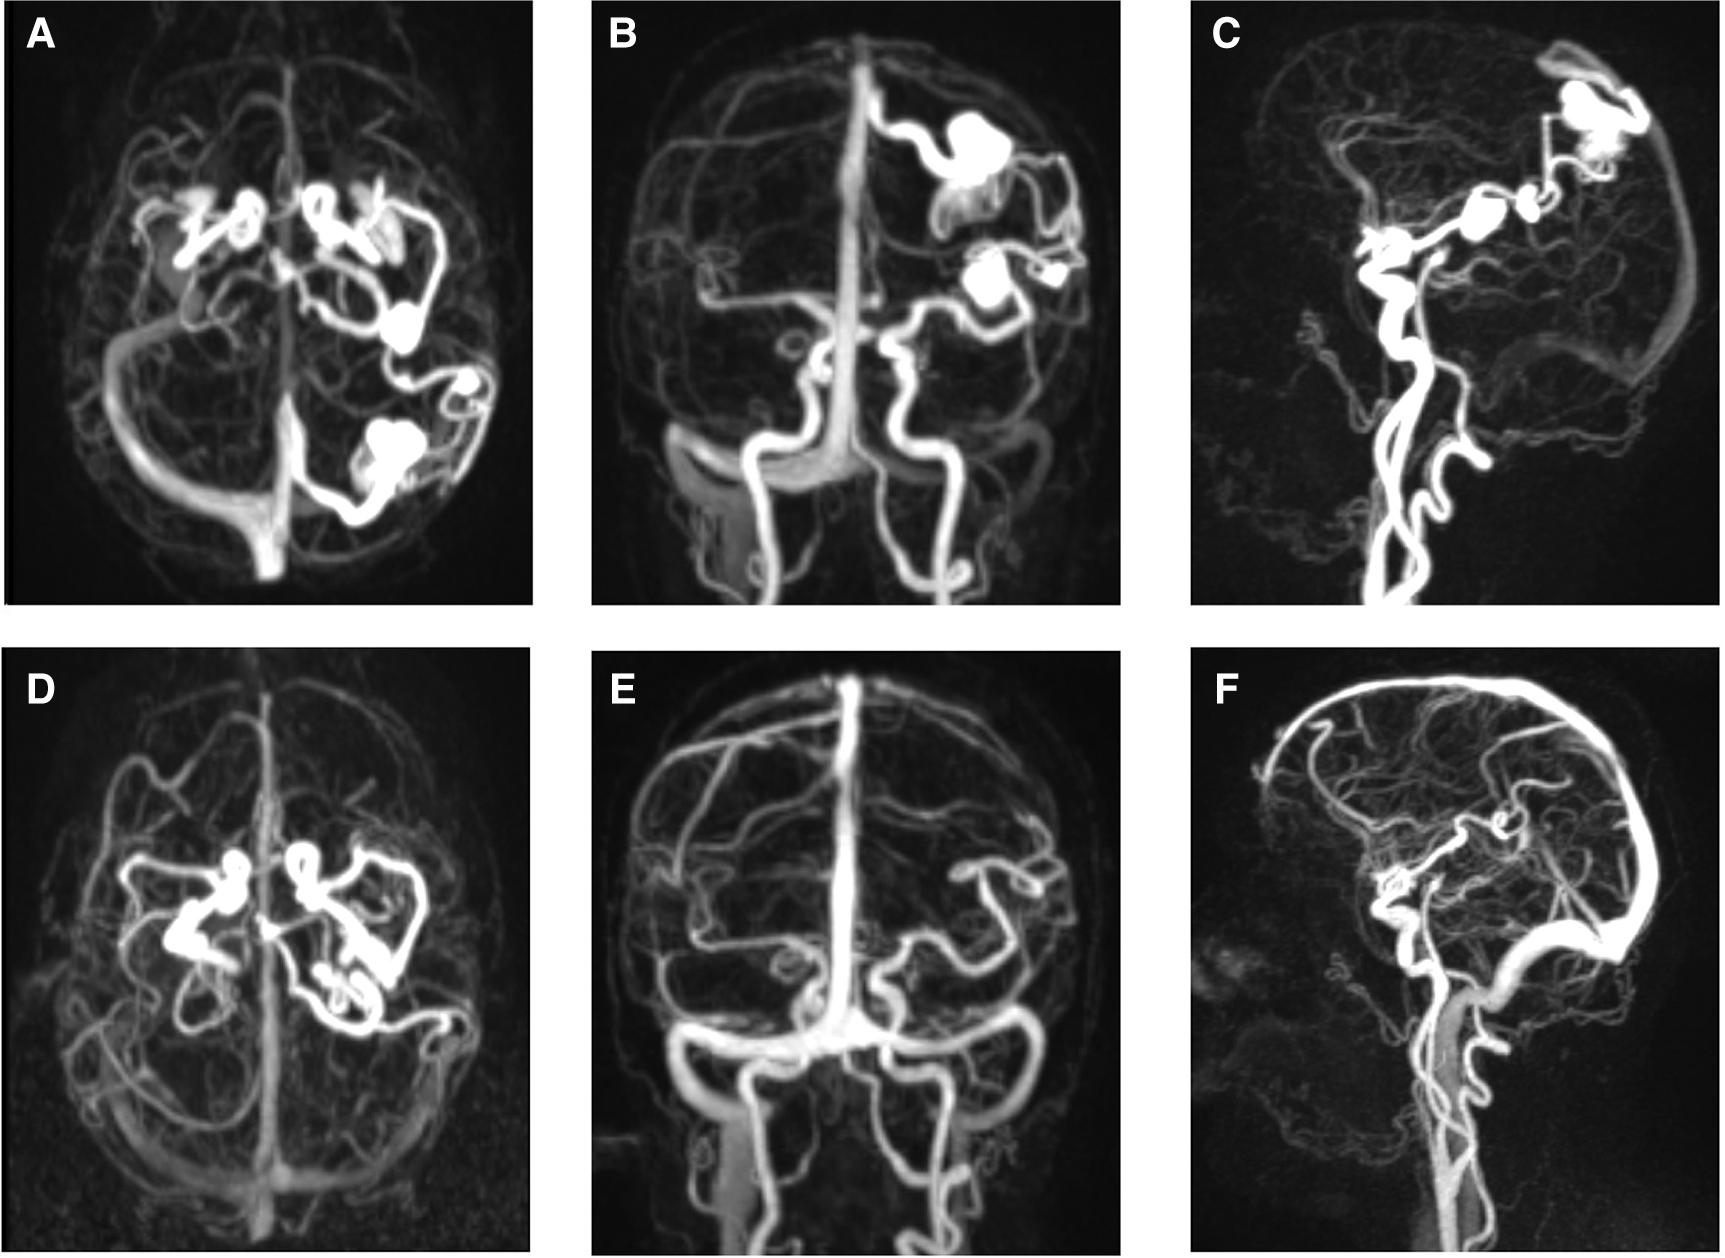

Figure 2

Early, middle, and late phases of DSA. (A–C) Sagittal (lateral) and (D–F) coronal (anterior-posterior) angiograms (views) demonstrating the adjacent flow-related MCA aneurysms on the left side with the associated BAVM. Note the presence of the BAVM venous ectasia in the later phase (C,F).

Figure 3

TWIST MR angiography before and after BAVM elimination. (A–C) Axial, coronal, and sagittal TWIST (time-resolved angiography with interleaved stochastic trajectories) MR angiography depicting both flow-related MCA aneurysms and associated BAVM. (D–F) Complete regression of the flow-related MCA aneurysms following the encounter of BAVM elimination.